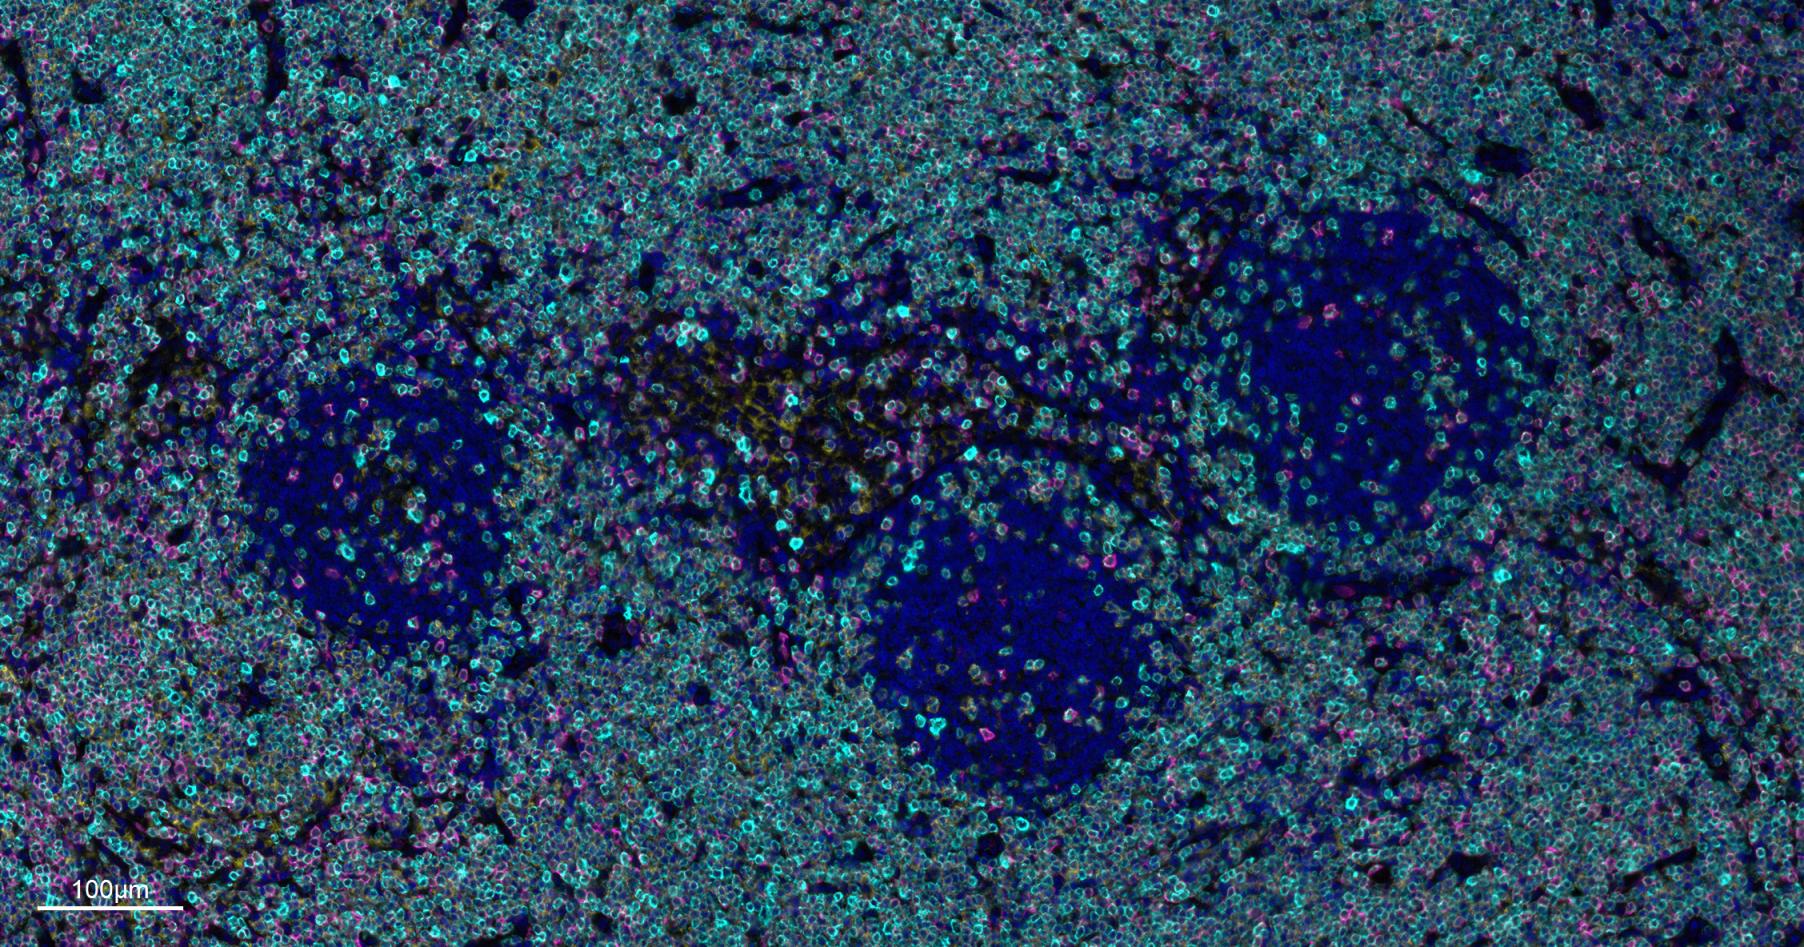

Paraformaldehyde-fixed, paraffin embedded Human Tonsil. Merged staining of anti-CD8A (bsm-34251M; 1:200; pink) anti-CD4 (bsm-52469R; 1:200; light blue) anti-CD3E (bsm-60002R; 1:200; green) anti-CD68 (bsm-60634R; 1:200; white) anti-CD11c (bsm-61135R; 1:200; orange) and anti-CD20 (bsm-63327R; 1:200; yellow) DAPI (dark blue) was used as a nuclear counter stain.